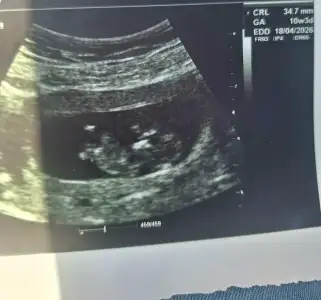

Ramzi teorisi doğru mu? Keseye göre cinsiyet tahmini yapar mısınız?